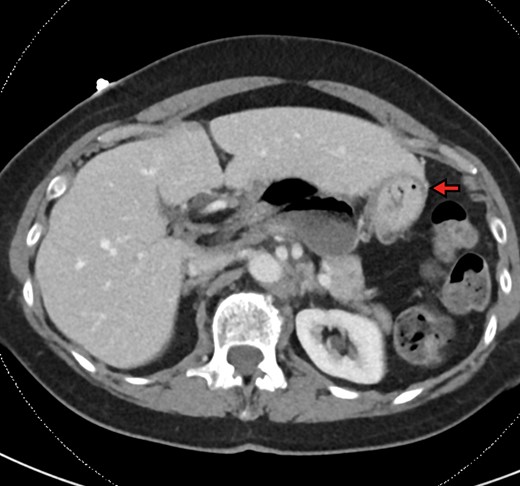

The patient is a 70-year-old woman who presented to the emergency department with acute-onset abdominal pain throughout her epigastrium for approximately 2 hours. The pain was constant and severe, extending across the bilateral upper quadrants. She had experienced pain like this once before within the past year which spontaneously resolved within 4 hours. The patient’s last oral intake was an hour before onset of the pain, and she denied any fevers, chills, nausea or vomiting. She was an otherwise healthy woman who took no medications and had no abdominal surgical history. On admission, vital signs were normal, with a heart rate in the 70’s. Although initially reported as tender by emergency department staff, after pain medication and intravenous fluids, examination by the surgical team revealed resolution of pain and a soft, non-tender abdomen. Lactic acid on presentation was 5.0 mmol/l, and her white blood cell count was 9600 µl−1, with the remainder of her laboratory values within normal limits. She underwent a computed tomography scan which demonstrated herniation of her cecum through the FoW, causing compression of the inferior vena cava (IVC) and portal vein (Figures 1–3).

The cecum is absent from the right lower quadrant and is located between the liver and stomach (red arrow) visualized as an air-fluid level (green arrow). Compression of the portal vein by herniated contents is demonstrated (blue arrow).